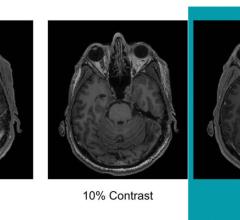

News | Computed Tomography (CT)

Canon Medical Systems recently introduced AiCE (Advanced intelligent Clear IQ Engine), a deep convolutional neural network (DCNN) image reconstruction technology for computed tomography (CT). AiCE uses deep learning technology to differentiate signal from noise so that it removes noise while it preserves true signal.